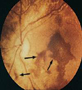

Hemorragia retiniana

Las hemorragias retinianas en el síndrome del niño sacudido son un signo importante. Son más frecuentes por debajo de los 18 meses de edad. Cualesquiera de los diferentes tipos de hemorragias se pueden ver en este síndrome pero las más frecuentes son la intraretineal y la preretineal ( hemorragia en forma de bote), esparcidas circunferencialmente alrededor del nervio óptico. Este tipo de hemorragia (en forma de bote) pueden irrumpir a través de la cara posterior del vítreo y extenderse dentro del mismo causando una hemorragia vítrea. La etiología de esta hemorragia es controvertida. Se plantean factores tales como el aumento de la presión intratorácica al comprimir el niño por el pecho lo que secundariamente producen un aumento de la presión venosa intracraneal, ocasionado la llamada retinopatía de Purtscher. El otro factor es por las lesiones que se producen en el cerebro causado por los movimientos de aceleración y deseleración. Estos provocan lagunas en los vasos de la retina e intracraneales y por consiguiente las hemorragias que pueden producir el llamado Síndrome o retinopatía de Terson.